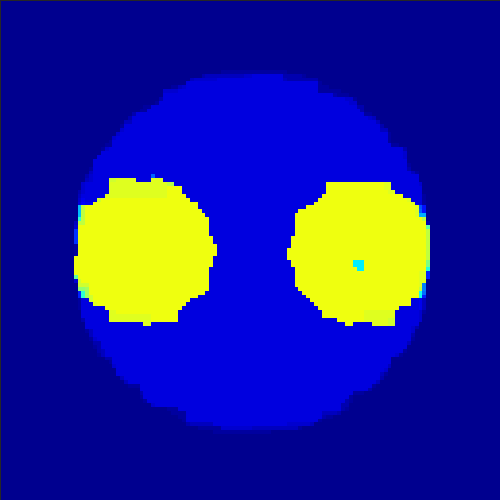

5.2 Monte Carlo Simulation

In order to test the behaviour of the proposed method in a more realistic, random-based test case, we performed a Monte Carlo simulation for dynamic SPECT imaging. First, we created a simple image phantom consisting of an outer and two inner circles which represents the structure of the region of interest (see figure 8(a)). Within those regions we assumed concentration curves over a time period of 90 time steps as displayed in figure 8(b). Based on the tracer intensity in an image frame at each time step, we created a variable number of random decay events (where the number is proportional to the average concentration in one pixel in the whole image frame per time step) with a probability proportional to the concentration in every subregion. They are detected by a virtual double head gamma camera rotating around the patient by 46 degrees per time step, which consists of 374 detector bins. Every simulated decay event is projected onto the scanner and counted by the corresponding detector bin.

In two different tests we fixed the number of events counted by the detector equal to (resp. ) times the average concentration in one pixel. The resulting sinogram images of the accumulated counts in each bin are shown in figure 9.

Based on the sinogram data we applied the proposed algorithm in order to reconstruct the original image sequence. The results for both test cases are shown in figure 10.

As one can see, the method is able to reconstruct the regions properly, even in case of a low count number. Within a number of iterations (average of 100 outer and 10000 inner iterations), the algorithm presents a reasonable reconstruction of the region of interest and the corresponding regional tracer concentration curves. Here, the parameters were not optimized as in the case of the synthesized data sets in the previous section, but kept fixed as , and . With futher optimized parameter values one could possibly provide even better results.